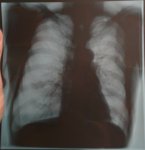

IMG20251016095724.jpg

Где пиздецома?

Аноним 16/10/25 Чтв 08:58:50 #15 №325599636

>>325599617

Аноним 16/10/25 Чтв 09:07:34 #18 №325599870

>>325599775

>>325598846

бля, тут какая то и слева и справа огромные пиздецомы

>>325598833

тут справа что- то удаляли, все средостение смещено.